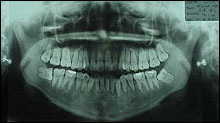

@Charting